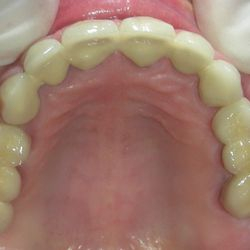

Ο 35χρονος αυτός ασθενής προσήλθε στο ιατρείο παραπονούμενος για το χρώμα και το σχήμα των άνω προσθίων δοντιών του καθώς και για το χρώμα των κάτω προσθίων δοντιών του.

Μετά από ένα βαθύ καθαρισμό των δοντιών, αποφασίστηκε να αποκατασταθούν τα άνω δόντια με νέες ολοκεραμικές όψεις και γέφυρες για σωστή απόδοση χρώματος και σχήματος.

Το χρώμα των κάτω δοντιών βελτιώθηκε μετά απο 3 συνεδρίες λεύκανσης στο ιατρείο.